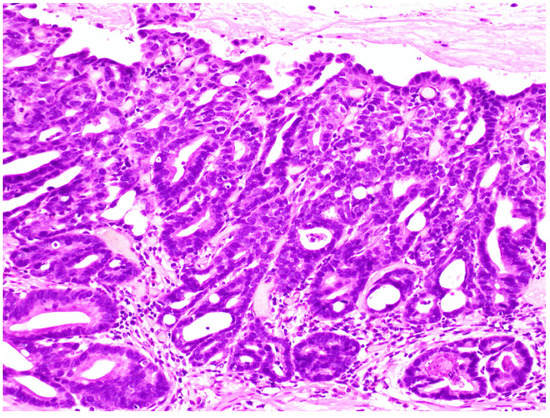

Figure 3.

Intramucosal adenocarcinoma. Glands have a complex architecture with irregular branching and glandular anastomosis. Invasion into the lamina propria with no evident desmoplastic reaction.